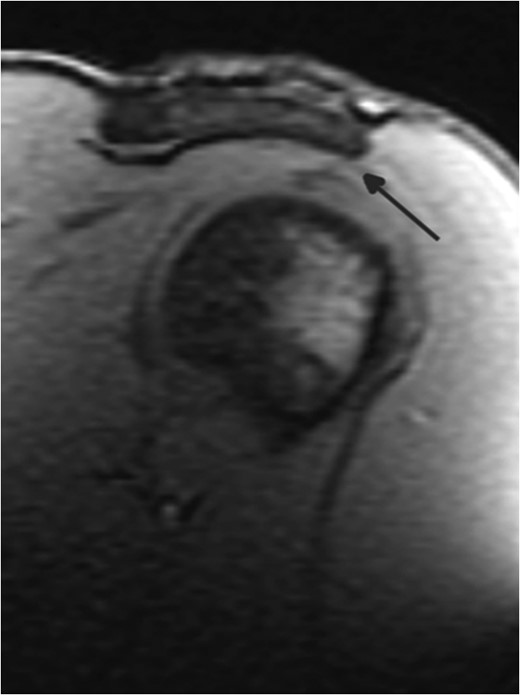

Down-sloped or hooked acromion morphologies may cause bony encroachment on the soft tissues of the subacromial space, predisposing to shoulder impingement syndrome. Of the latter, a hooked or Type III acromion (T3A) has also been linked to rotator cuff (RC) pathology. However, as bony acromial impingement is typically thought to occur over the age of 40, its occurrence in younger shoulder athletes presenting with shoulder pain, impingement and RC pathology may be overlooked. This case serves to illustrate the occurrence of T3A in a younger shoulder athlete, and the importance of early imaging in achieving diagnostic accuracy. Appropriate surgical referrals are patients with subacromial impingement syndrome refractory to 3–6 months of appropriate conservative treatment. Surgery may be particularly beneficial in patients with a T3A.

The initial diagnostic impression was of chronic left shoulder impingement (query subacromial bursal effusion, early rotator cuff (RC) tear, down-sloped acromion), and mild ACJ osteoarthritis. Although the physical examination was generally unremarkable, the history was indicative of some mild left extensor origin biceps tendonopathy.

Some studies have identified a significant association between Type III acromial morphology and full thickness RC tears [4].

Neer concluded that 95% of RC tears are caused by mechanical impingement [7], associating RC tears with extremely hooked (>43°) anterior acromial slope. Other studies have looked at the lateral extension and angulation of the acromial slope also being important in diagnosing and managing impingement pathologies [8].

Although thought to be associated with older populations, T2 down-sloped and T3 hooked acromial impingement may occur in younger populations such as overhead athletes. Impingement may be manifested by pain with overhead activities, shoulder weakness and decreased range of motion. Early shoulder X-rays including the outlet ‘Y’ view to define acromial morphology [9], or MRI imaging may help to refine diagnosis, prevent inappropriate therapies, understand prognosis and expedite more effective management strategies.